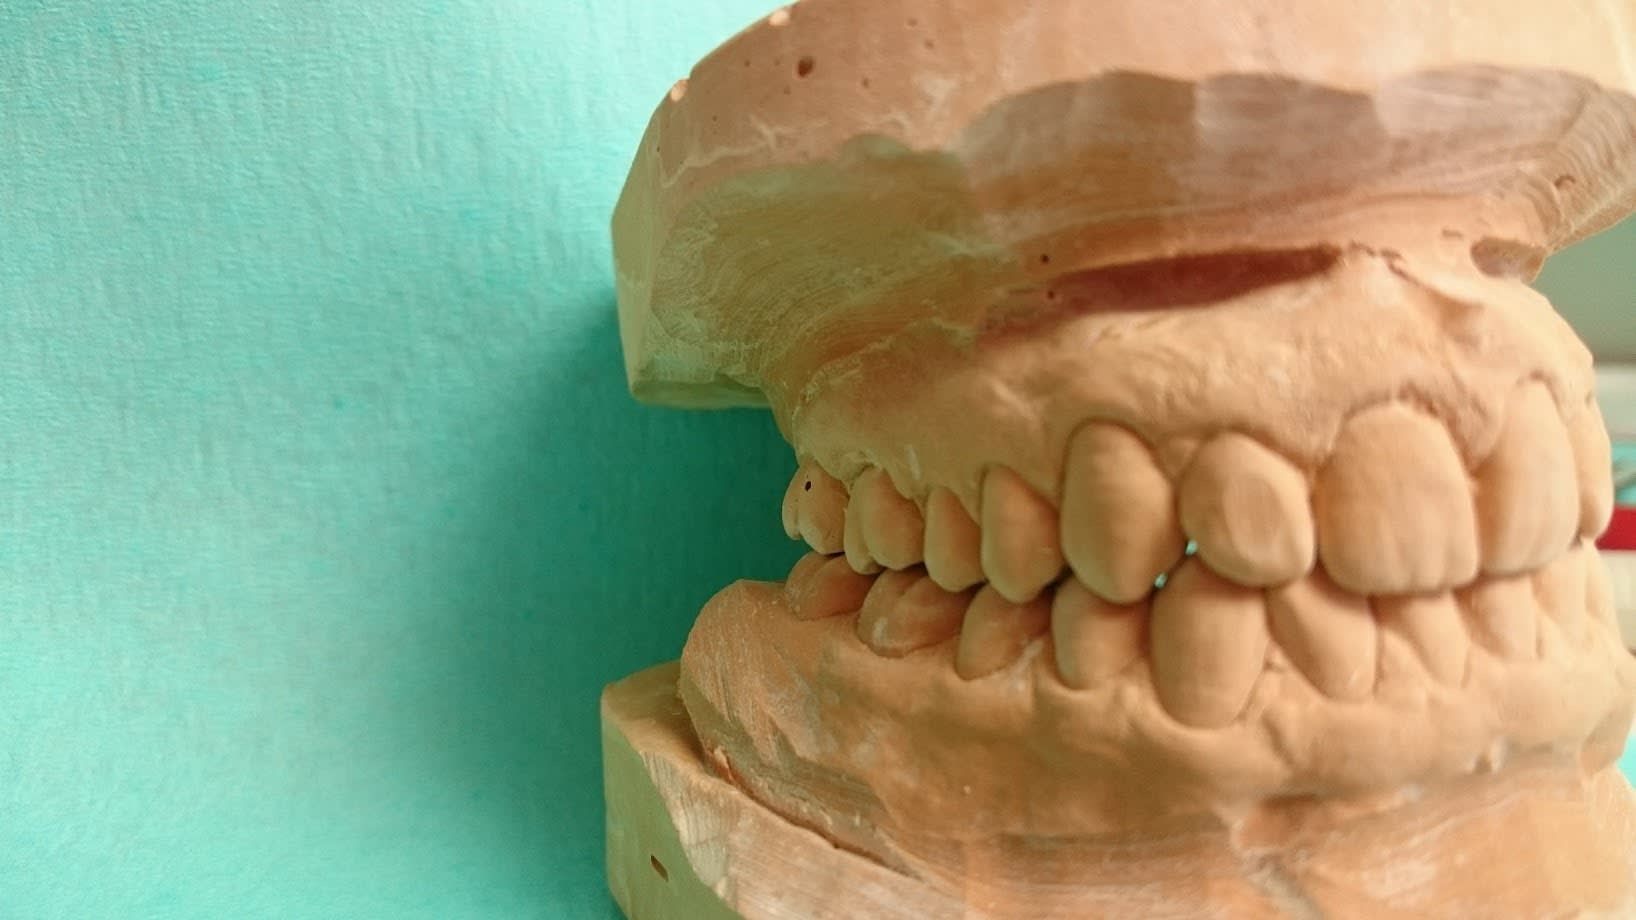

Ahh oui je suis bête pour les PAP ... mais alors sur de la fixe de grande étendue ...? Sinon quel rapport avec les amygdales ? tiens aller une partie de mon anatomie !:

Dsc 0780 hgb3om - Eugenol

Dsc 0782 anpnxt - Eugenol

Casa , ta 23 est naturelle ?

dommage que je ne puisse te voir par derriere .

en occlusion ,bien sur :-)

Houlà , faut que je réponde là !! alors oui enlaye , tout est naturel chez moi ! pas une couronne, seulement une 15 dévitalisée (erreur de jeunesse à la fac)et non couronnée depuis 10 ans facile (tu vois chicot ça peut se faire si on a une bonne occlusion , une bonne hygiène et je ne suis pas une forcenée de la brosse à dent ! ) ce qui m'amène à ton cas : tu lui a fais quoi sur cette 16 à part l'endo il y a 11 ans ? rien peut-être et regarde la 15 en 11 ans complètement rongée .... donc le mec il a un fort pouvoir carieux et c'est avec des gars comme ça qu'on peut se prendre pour le (la) pire des nazes ! même couronnée , elle serait partie en sucette cette dent ... (il me semble que tu as un exemple proche ...) donc ton exemple ne démontre rien . Quant à ton 2 ème cas , comme Enlaye , SC33 , , ça vaut le coup , sinon t'es sur d'avoir de gros pb paro assez rapidement ...